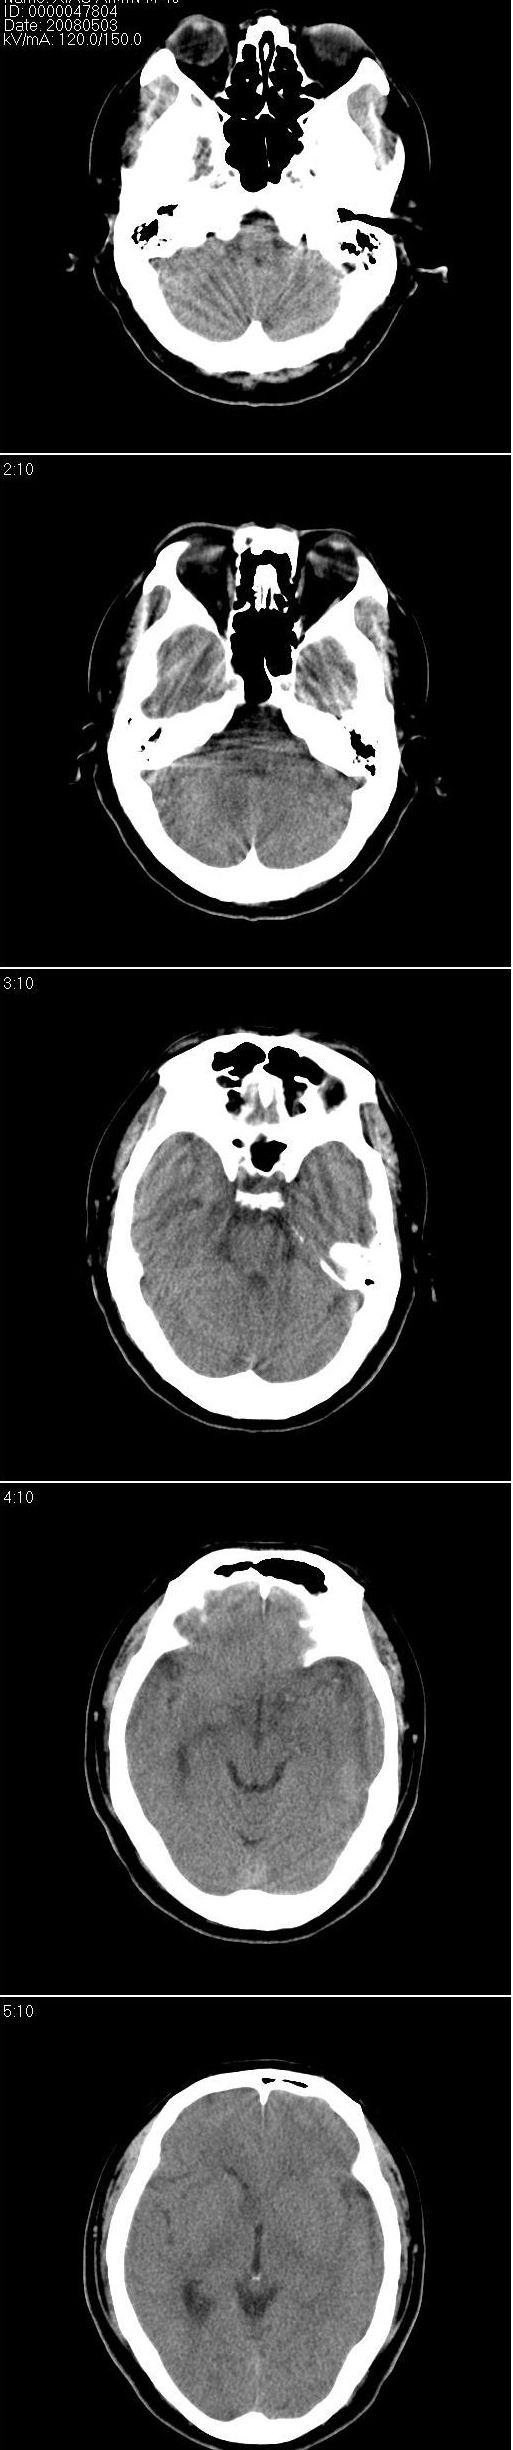

以下是引用liuyue在2008-5-3 15:51:00的发言:[br]右侧侧脑室室间孔处似可见等密度影,右侧侧脑室扩大,但前角及下角无明显扩张变园钝,建议:薄层扫描或强化ct扫描或mri检查。

以下是引用zhengfaming在2008-5-3 20:30:00的发言:[br]右侧侧脑室室间孔处似可见等密度结节影(图2),右侧侧脑室扩大,考虑占位.以室管膜瘤可能性大